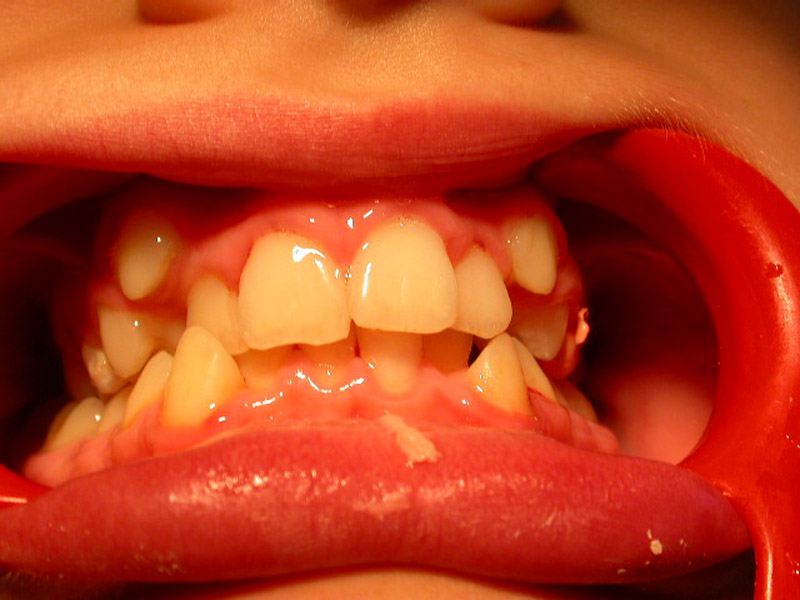

Caries

How caries occurs?

Caries is a disease. It is the most widespread disease in the world. The bacterial dental plaque (also called a biofilm) is the main cause of the infection of the teeth and the supportive tissues, i.e. of the caries and periodontal diseases respectively. The accumulation of dental plaque and the colonization of bacteria lead to the appearance of dental and periodontal pathology.

Microbes cling on various surfaces and form the biofilm. In addition, frequent intake of carbohydrates (especially sweets) gets metabolized to acids. The pH of dental plaque becomes acidic repeatedly, and that favors acid tolerant bacteria, such as streptococci and lactobacilli that are the most dangerous bacteria for caries.